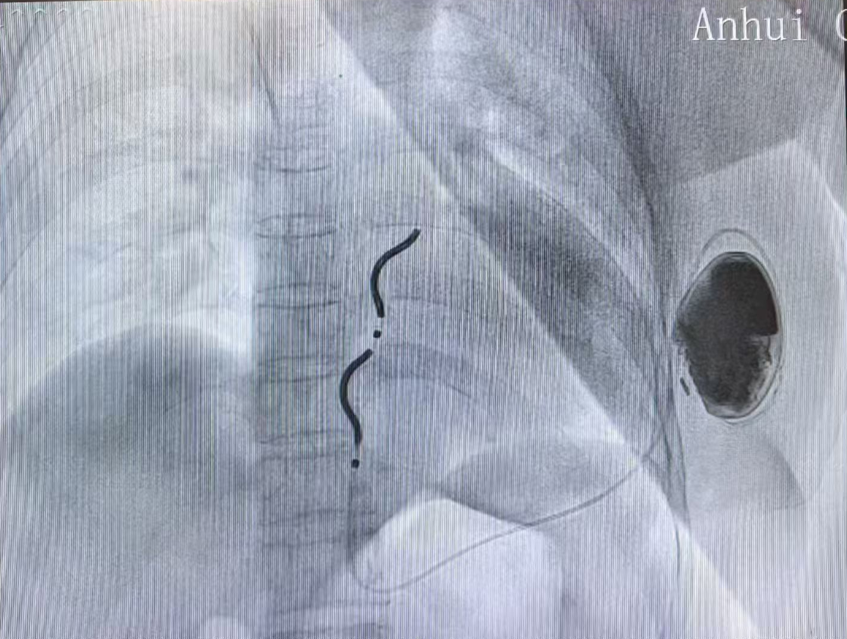

本例患者为59岁女性,扩张性心肌病病史多年,入院检查心脏超声EF25%,并且反复发作持续性室性心动过速,具有心源性猝死二级预防的适应证。在与患者及其家属充分沟通后决定植入EV-ICD血管外除颤器。术前乔青教授团队通过胸部CT仔细评估患者解剖结构,规划电极植入路径,与心外科专家、麻醉医师共同讨论手术操作细节,对术中可能遇到的问题进行了充分的讨论和准备,制定了完善的手术预案。11月11日下午植入EV-ICD,手术过程顺利,胸骨下电极稳定,电学参数正常,除颤测试通过。患者麻醉苏醒后即转回普通病房,状态良好。

Aurora EV-ICD 结合了现有经静脉和皮下ICD系统的优势,既不需要将电极植入心脏和血管内,同时实现了完整的除颤复律和抗心动过速起搏(ATP)治疗功能,装置体积小,预估使用寿命长达11.7年,为患者减少了未来设备更换的次数和经济负担。同时兼容1.5T 和3.0T MRI 全身磁共振扫描,术后更加美观舒适,不影响患者日常生活,是室性心律失常治疗及心脏性猝死防治领域的又一大技术突破。